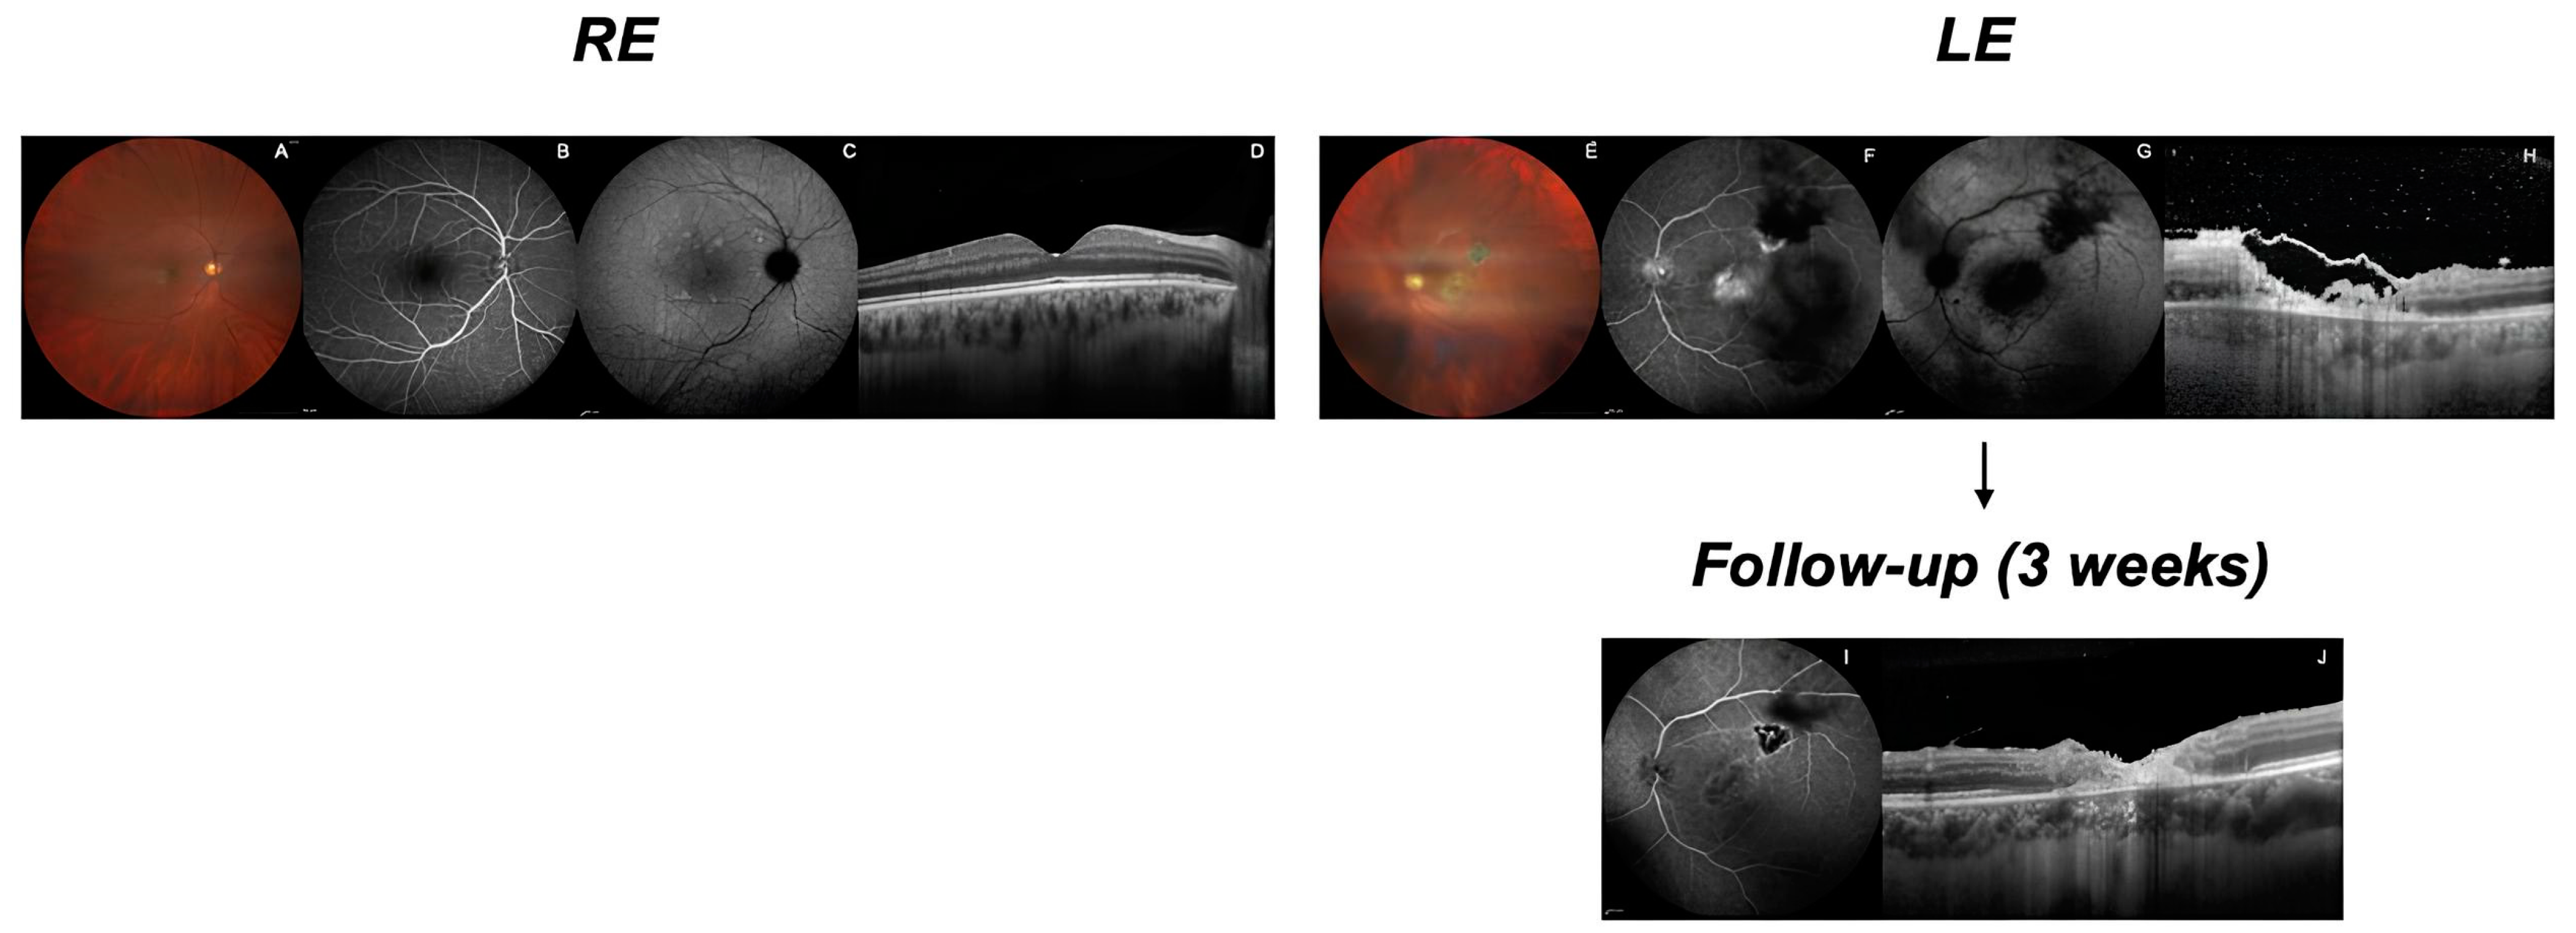

Upon initial examination, his best-corrected visual acuity (BCVA) was 20/20 in the right eye (RE) and 20/200 in the LE according to the Snellen chart. The ophthalmoscopic examination and fundus photography of the RE did not reveal any pathological alterations (Figure 1A), while the LE showed significant vitreous turbidity and a focus of chorioretinitis in the fundus (Figure 1E). We conducted a comprehensive multimodal imaging assessment, including fluorescein angiography (FA), optical coherence tomography (OCT), and indocyanine green angiography (ICGA) (Figure 1).

Figure 1.

Multimodal imaging of both eyes at initial presentation and 3-week follow-up. Right Eye (RE): (A) Color fundus photograph showing normal appearance. (B) Fluorescein angiography with normal circulation. (C) Indocyanine green angiography revealing mild choroidal hyperpermeability in late phase. (D) Optical coherence tomography demonstrating normal retinal architecture. Left Eye (LE) at presentation: (E) Color fundus photograph showing vitreous haze and chorioretinal lesion. (F) FA revealing hypofluorescent lesion with hyperfluorescent margins and multiple dark areas due to vitreous debris. (G) ICGA displaying hypocyanescent area in supero-temporal region. (H) OCT showing severe disruption to retinal layers and the presence of cellularity. LE at 3-week follow-up: (I) FA demonstrating reduction in lesion activity and vitreous haze. (J) OCT revealing persistent structural changes, but decreased vitreous cellularity.

The initial FA revealed normal circulation times in the RE (Figure 1B), while the LE showed early macular hypofluorescence and late irregular hyperfluorescence due to window defects from retinal pigment epithelium (RPE) atrophy and retinal disruption in the center of the macula (Figure 1F). Notably, the late-phase FA reveals a well-demarcated hypofluorescent lesion in the supero-temporal sector, suggestive of chorioretinal toxoplasmosis scarring. At the margins of this lesion, there is mild hyperfluorescence, which is suggestive of modest late staining (Figure 1F). Significantly, multiple dark areas were observed throughout the image, particularly prominent in the superior and temporal regions. These areas of hypofluorescence represent blocking or shadowing effects, consistent with vitreal inflammation or debris. ICGA showed choroidal hyperpermeability in the RE in the late phase (Figure 1C), while the LE displayed an area of early cyanescence in the macular region and a supero-temporal hypocyanescent area increasing in intensity in the late phases, corresponding to the location of the active toxoplasmic lesion (Figure 1G). Structural OCT of the LE in the macular region revealed the severe disorganization of the retinal architecture (Figure 1H). The image revealed significant disruption to the inner retinal layers, with areas of hyper-reflectivity and shadowing consistent with active inflammation and possible necrosis. In contrast, structural OCT of the RE appeared to be within the normal limits, showing no significant abnormalities (Figure 1D).

Based on the clinical presentation and imaging findings, we suspected ocular toxoplasmosis. Blood tests were performed, revealing significantly elevated Toxoplasma IgG (210 U/mL) levels, while the IgM levels were within the normal range (3.6 U/mL). The high IgG avidity (0.537) was indicative of chronic infection reactivation. It is worth noting that in cases of toxoplasmosis reactivation, the IgM levels may not be elevated, as observed in our patient [6]. Treatment was initiated with oral prednisone (25 mg daily) and trimethoprim/sulfamethoxazole (160 mg/800 mg combination, thrice daily). At the 3-week follow-up, the patient continued with the initial regimen of three tablets of trimethoprim/sulfamethoxazole and one tablet of dexamethasone daily, with no changes made to the therapy for neurosarcoidosis, in accordance with the rheumatologist’s recommendations. Given the observed improvement in the patient’s clinical condition, we planned to continue this treatment for an additional 7 days. Following this, we began the tapering process, reducing the trimethoprim/sulfamethoxazole dosage to two tablets per day and the dexamethasone dosage to half a tablet per day. The ultimate goal was to achieve a preventive dosing schedule of one tablet of trimethoprim/sulfamethoxazole every 3 days [6]. At the 3-week follow-up, the patient showed significant improvement. While the BCVA remained unchanged (Snellen: RE 20/20, LE 20/200), there was a marked reduction in vitreous turbidity in the LE, with no evidence of active vitreitis. FA of the LE demonstrated a notable decrease in vitreous haze, indicating reduced vitreous activity. The supero-temporal lesion in the LE showed slightly hyperfluorescent margins, but to a lesser extent than initially observed, suggesting decreased lesion activity (Figure 1I). OCT of the LE revealed persistent structural changes in the retina, but the previously noted vitreous cellularity was no longer visible (Figure 1J). These findings in the LE indicate a positive response to the treatment, with a reduction in active inflammation.